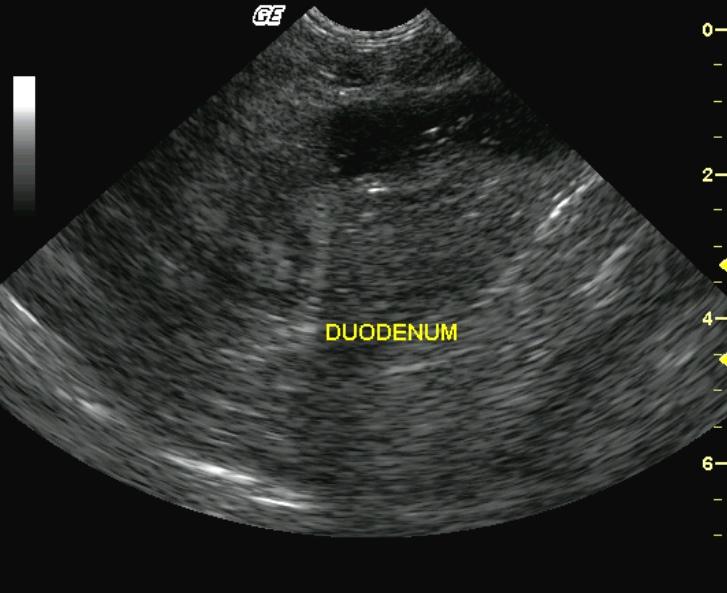

This 4-year-old MN Himalayan cat was presented for 3 days of persistent vomiting, lethargy, and anorexia. The physical exam revealed moderate dehydration and tense abdomen; the cat would not allow deep palpation. The CBC revealed moderate leukocytosis with a left shift. Blood chemistry demonstrated moderate azotemia, mild hyperglycemia, mild hyponatremia and hypochloremia. The urine was concentrated with minor proteinuria.